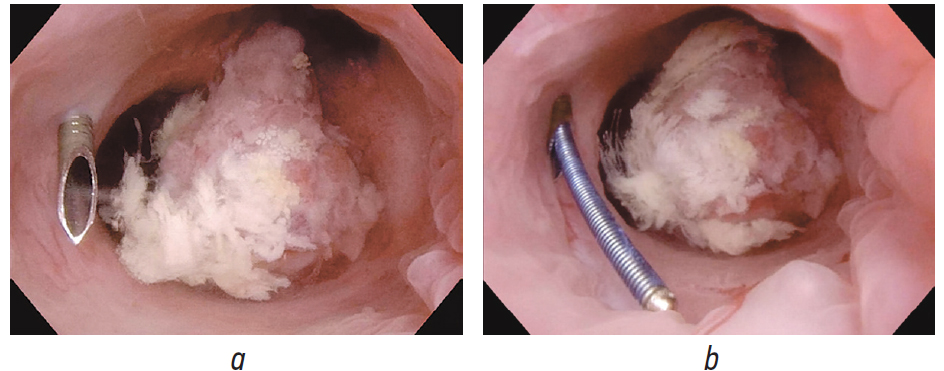

Принято решение о повторном оперативном лечении перкутанным доступом. В положении пациента на животе под эндотрахеальным наркозом выполнена пункция полостной системы правой почки через нижнюю группу чашек, пункционный тракт бужирован до 24 Ch и установлен кожух Амплатц. С помощью гибкого видеонефроскопа произведена ревизия полостной системы правой почки, в проекции зоны предыдущей резекции опухоли отмечается рубцово-измененная стенка лоханки, в области рубца рецидива новообразования не выявлено. При дальнейшей ревизии полостной системы правой почки в проекции верхних групп чашек выявлена крупная опухоль крупноворсинчатой структуры на широком основании (рис. 7). Выполнить ее резекцию не представлялось возможным из-за острого угла «атаки» и невозможности адекватно провести инструмент в верхнюю группу чашек. Принято решение о применении дополнительного перкутанного доступа в проекции верхних групп чашек. Под ультразвуковым и визуальным контролем прецизионно был произведен второй доступ в верхнюю группу чашек вблизи с новообразованием (рис. 8).

Рис. 8. Прецизионный доступ в верхнюю группу чашек правой почки под эндоскопическим контролем: а — кончик пункционной иглы 18G; b — струна проводник в полостной системе почки

Fig. 8. Precision access to the upper group of calyces of the right kidney under endoscopic control: a, tip of the puncture needle 18G; b, string conductor in the pelvicalyceal system of the kidney